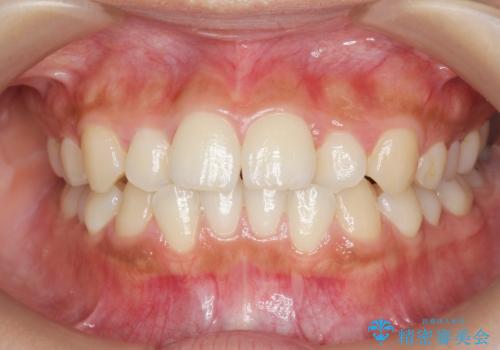

【モニター】八重歯と前歯のクロスバイト ワイヤーを併用しインビザラインで矯正治療